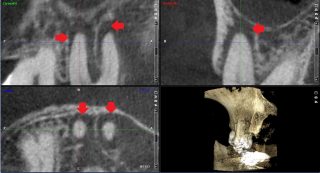

それでは、実際のCTスキャン画像をみながら説明いたします。以下は、根管治療時のCTスキャン画像です。左のレントゲン画像の歯のCT画像が右にあります。レントゲン画像では確認できなかった根尖病巣の黒い影(赤い矢印の先の影)が、いずれもはっきり確認できます。

下のCT画像では、根管治療で見落とされているらしい根管(赤い矢印のところ)が確認できます。白い線状のものは根管の蓋、赤い矢印の先の黒い線状のものは根管に蓋がされていない状態です。根尖病巣(歯根をとり囲む影)の原因は、赤い矢印のところの未治療の根管の細菌感染が原因と思われます。